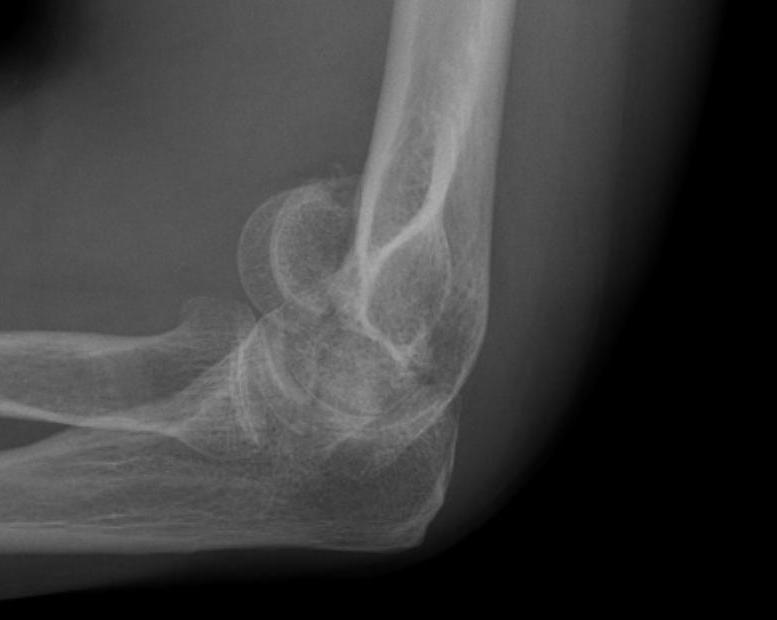

Coronal shear fracture of the distal humerus

Capitellum +/- trochlea

Bryan & Morrey Classification

| Type I | Type II |

Large osseous fracture of the capitellum

Articular cartilage injury with little bone |

Hanh Steinthal fracture

Kocher Lorenz fracture |